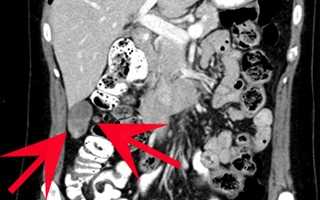

При воспалительных заболеваниях КТ помогает установить степень распространенности процесса, наличие абсцессов или флегмон. Например, при аппендиците исследование позволяет точно определить местоположение воспаленного отростка, его размеры и наличие осложнений. В случае заболеваний печени томография выявляет очаговые поражения, цирротические изменения и нарушения кровообращения. Метод особенно информативен при диагностике острых состояний — кишечной непроходимости, внутренних кровотечений и перфорации полых органов. Томография способна зафиксировать даже небольшие количества свободного газа в брюшной полости или жидкости в брюшине.